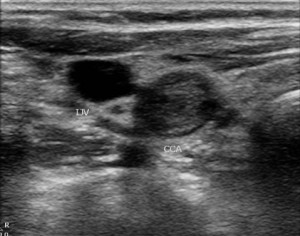

The diagnosis of carotid artery occlusion is made by vascular imaging. Duplex ultrasound can show absence of flow. The duplex can show thrombus in the artery and absence of flow with pulse wave and color Doppler. A clue to the diagnosis is the waveform in the common carotid artery. It becomes more high resistance than usual:

CTA can also show the occlusion and its extent.